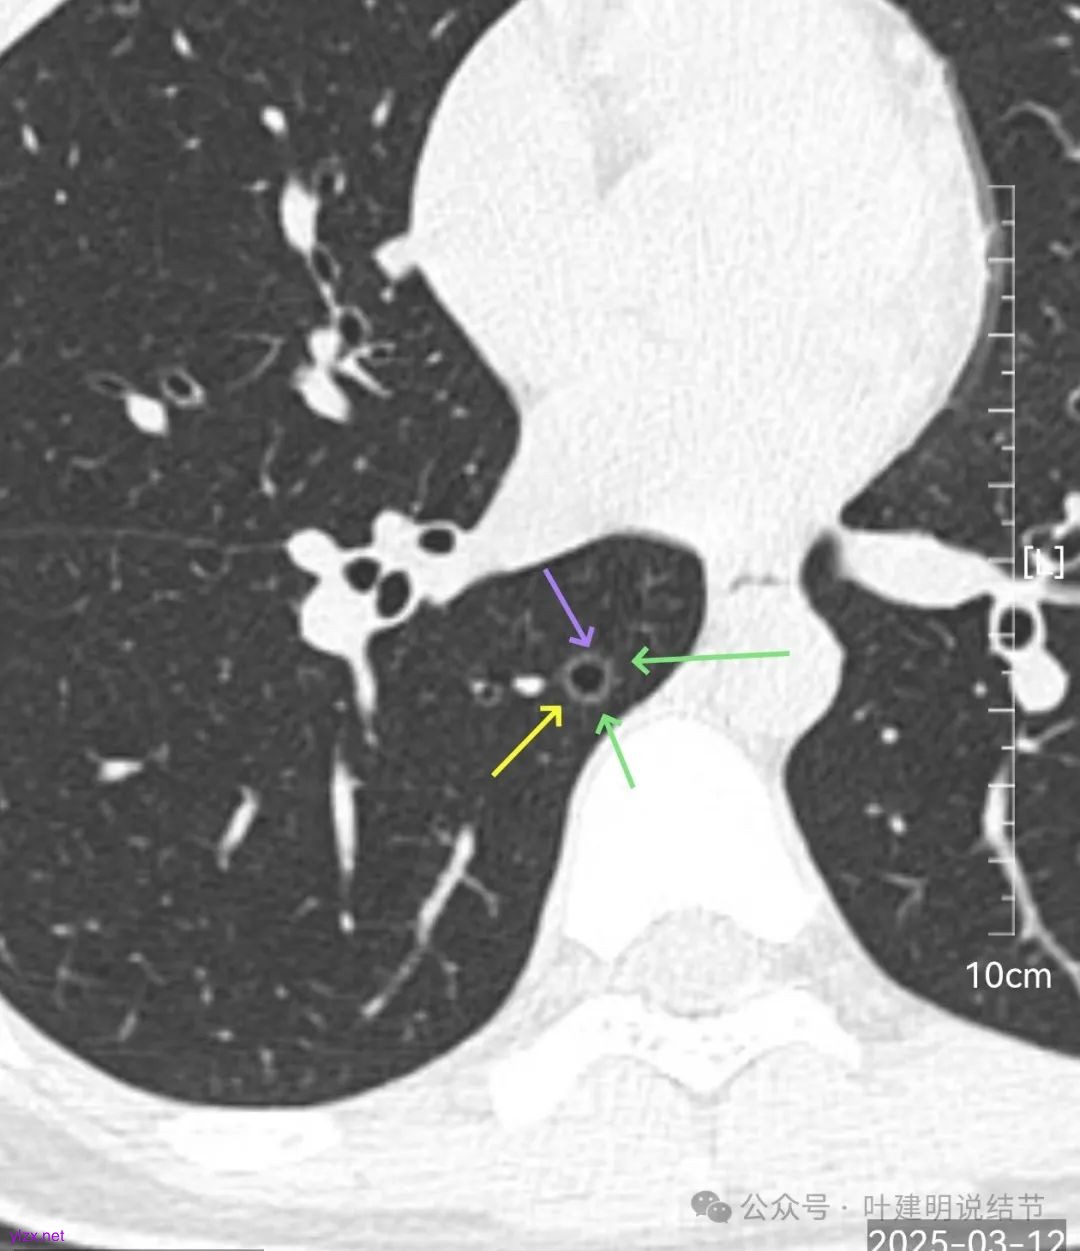

再来看风险最大的病灶6的连续层面:

血管从旁过,没有受结节影响。